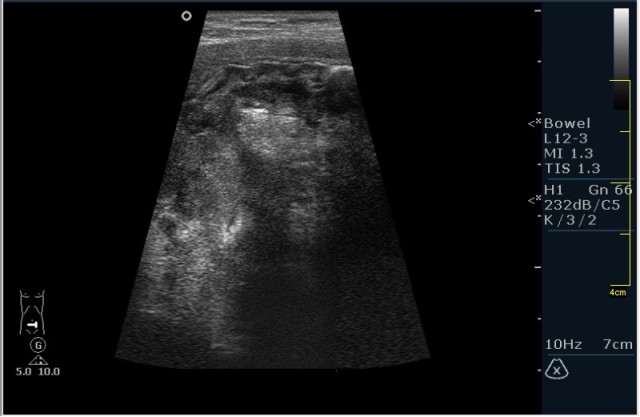

Пациент М. 60 лет с болями в левой подвздошной области. Пациент был направлен на УЗИ с диагнозом: левосторонняя почечная колика. Жалобы на боли в левой подвздошной области отдающие в таз. Анамнез без особонностей.

Пациента я сразу направил на эндоскопию. К сожалению, заключение было ожидаемым с моей стороны, опухоль (карцинома по результату биопсии).